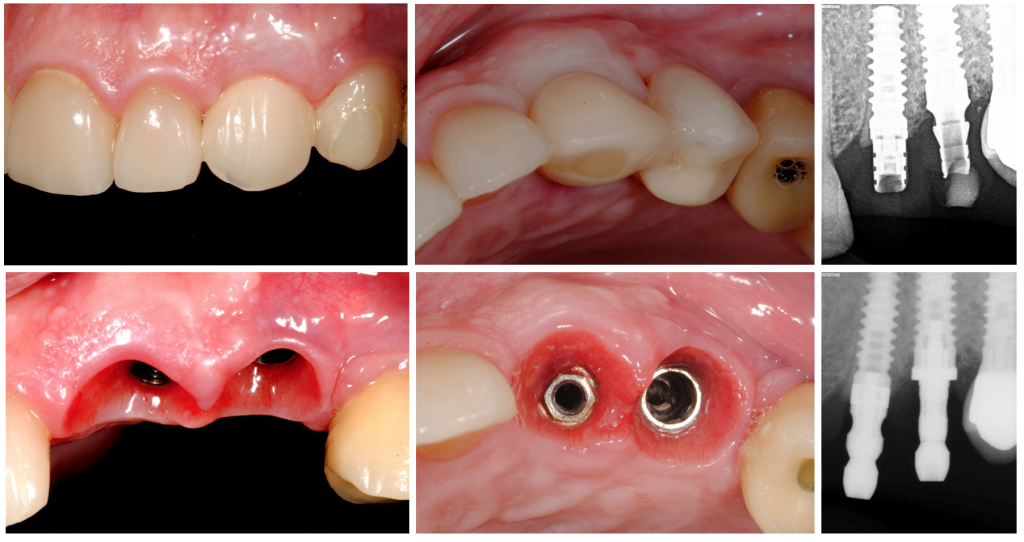

Eight months later, the provisional was substituted for a traditional zirconium crown, showing an amazing gingival architecture, which was seen as unchangeable after a 6th, 18th, and 24th month follow-up period.

In this case report, it was shown that the socket shield technique with immediate implant placement, as reported by HÜrzeller 2010, preserves the buccal cortical plate and healthy peri-implant tissues can be observed, showing to be one of the most conservative ridge preservation strategies for bone counters and gingival architecture preservation, and thought for getting a more aesthetic final result.